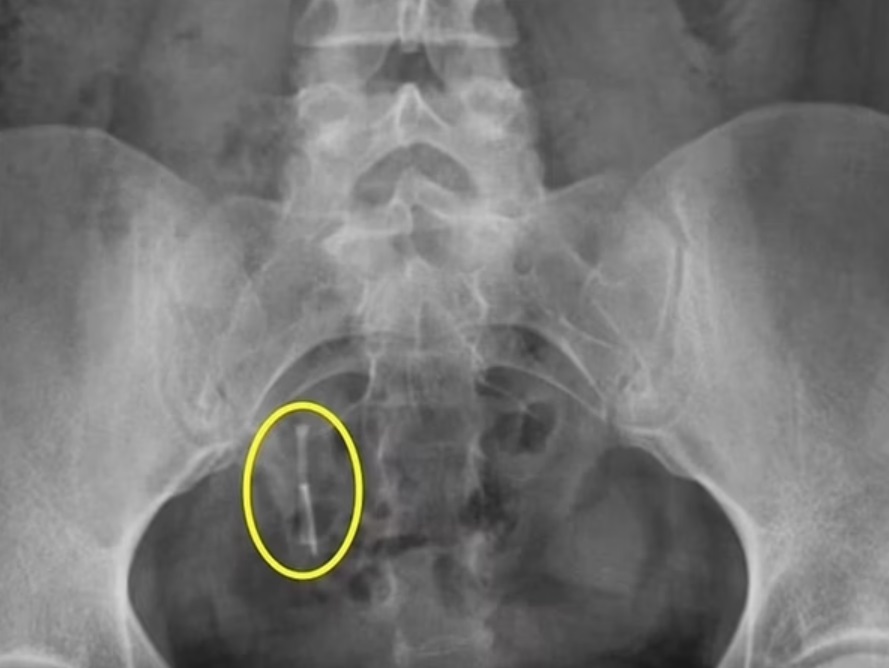

Posteriormente, Danielle começou a sentir dores na região do reto, mas os médicos não investigaram o sintoma. Anos depois, em abril de 2021, ela sofreu um acidente de carro e precisou realizar um raio-x. Não é que o DIU realmente foi localizado no cólon de Hampton?!

O DIU migrou para o local após perfurar o útero. “Foi uma loucura. Os médicos notaram um objeto estranho e eu mesma vi o raio-x. Pensei: ‘Uau, como isso ainda está dentro de mim?’. Finalmente senti que não estava louca”, relatou ela, em entrevista ao portal DailyMail.